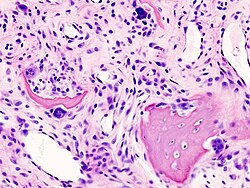

Patološka anatomija

Artroza je bolest koštano-mišićno-zglobnog sustava nastala uslijed trošenja hrskavice zbog prirodnog starenja, prethodnih oštećenja zglobova, te brojnih drugih etioloških faktora. Artroza predstavlja kroničnu degenerativnu promjenu jednog ili više zglobova, okarakteriziranu oštećenjem hrskavice koja prekriva zglobne površine i sekundarnim promjenama kosti koja leži ispod nje. Za razliku od drugih oblika artritisa (postoji oko 100 različitih vrsta), artroza nema utjecaja na unutarnje organe.

Kod artroze se hrskavica troši, povećavajući tako uzajamno trenje kostiju koje tvore zglob. To uzrokuje bol i oticanje, kao i gubitak pokretljivosti zgloba. Tijekom vremena, započinje prekomjerno izrastanje kosti duž zglobnog ruba kojeg nazivamo koštanim izraslinama ili osteofitima. Oni mogu pridonijeti gubitku pokreta u zglobu i povećanju osjećaja boli. Ove se izrasline mogu čak i slomiti i zaglaviti u zglobnom prostoru, što prouzrokuje još jače bolove i oštećenja.